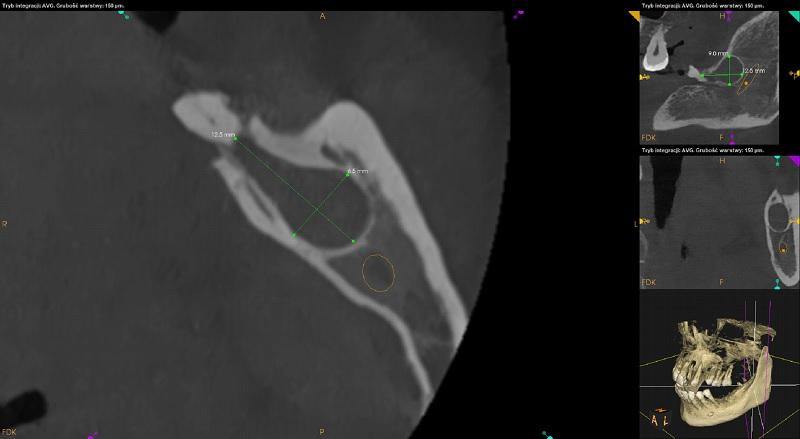

Korzeń resztkowy zęba 38. W okolicy okołowierzchołkowej rozległe ognisko osteolityczne (9mm x 12,5mm x 6,5mm).

Korzenie resztkowe zęba 46. W okolicy okołowierzchołkowej rozległe ognisko osteolityczne o nieregularnym kształcie (9mm x 12mm x 3,5mm).